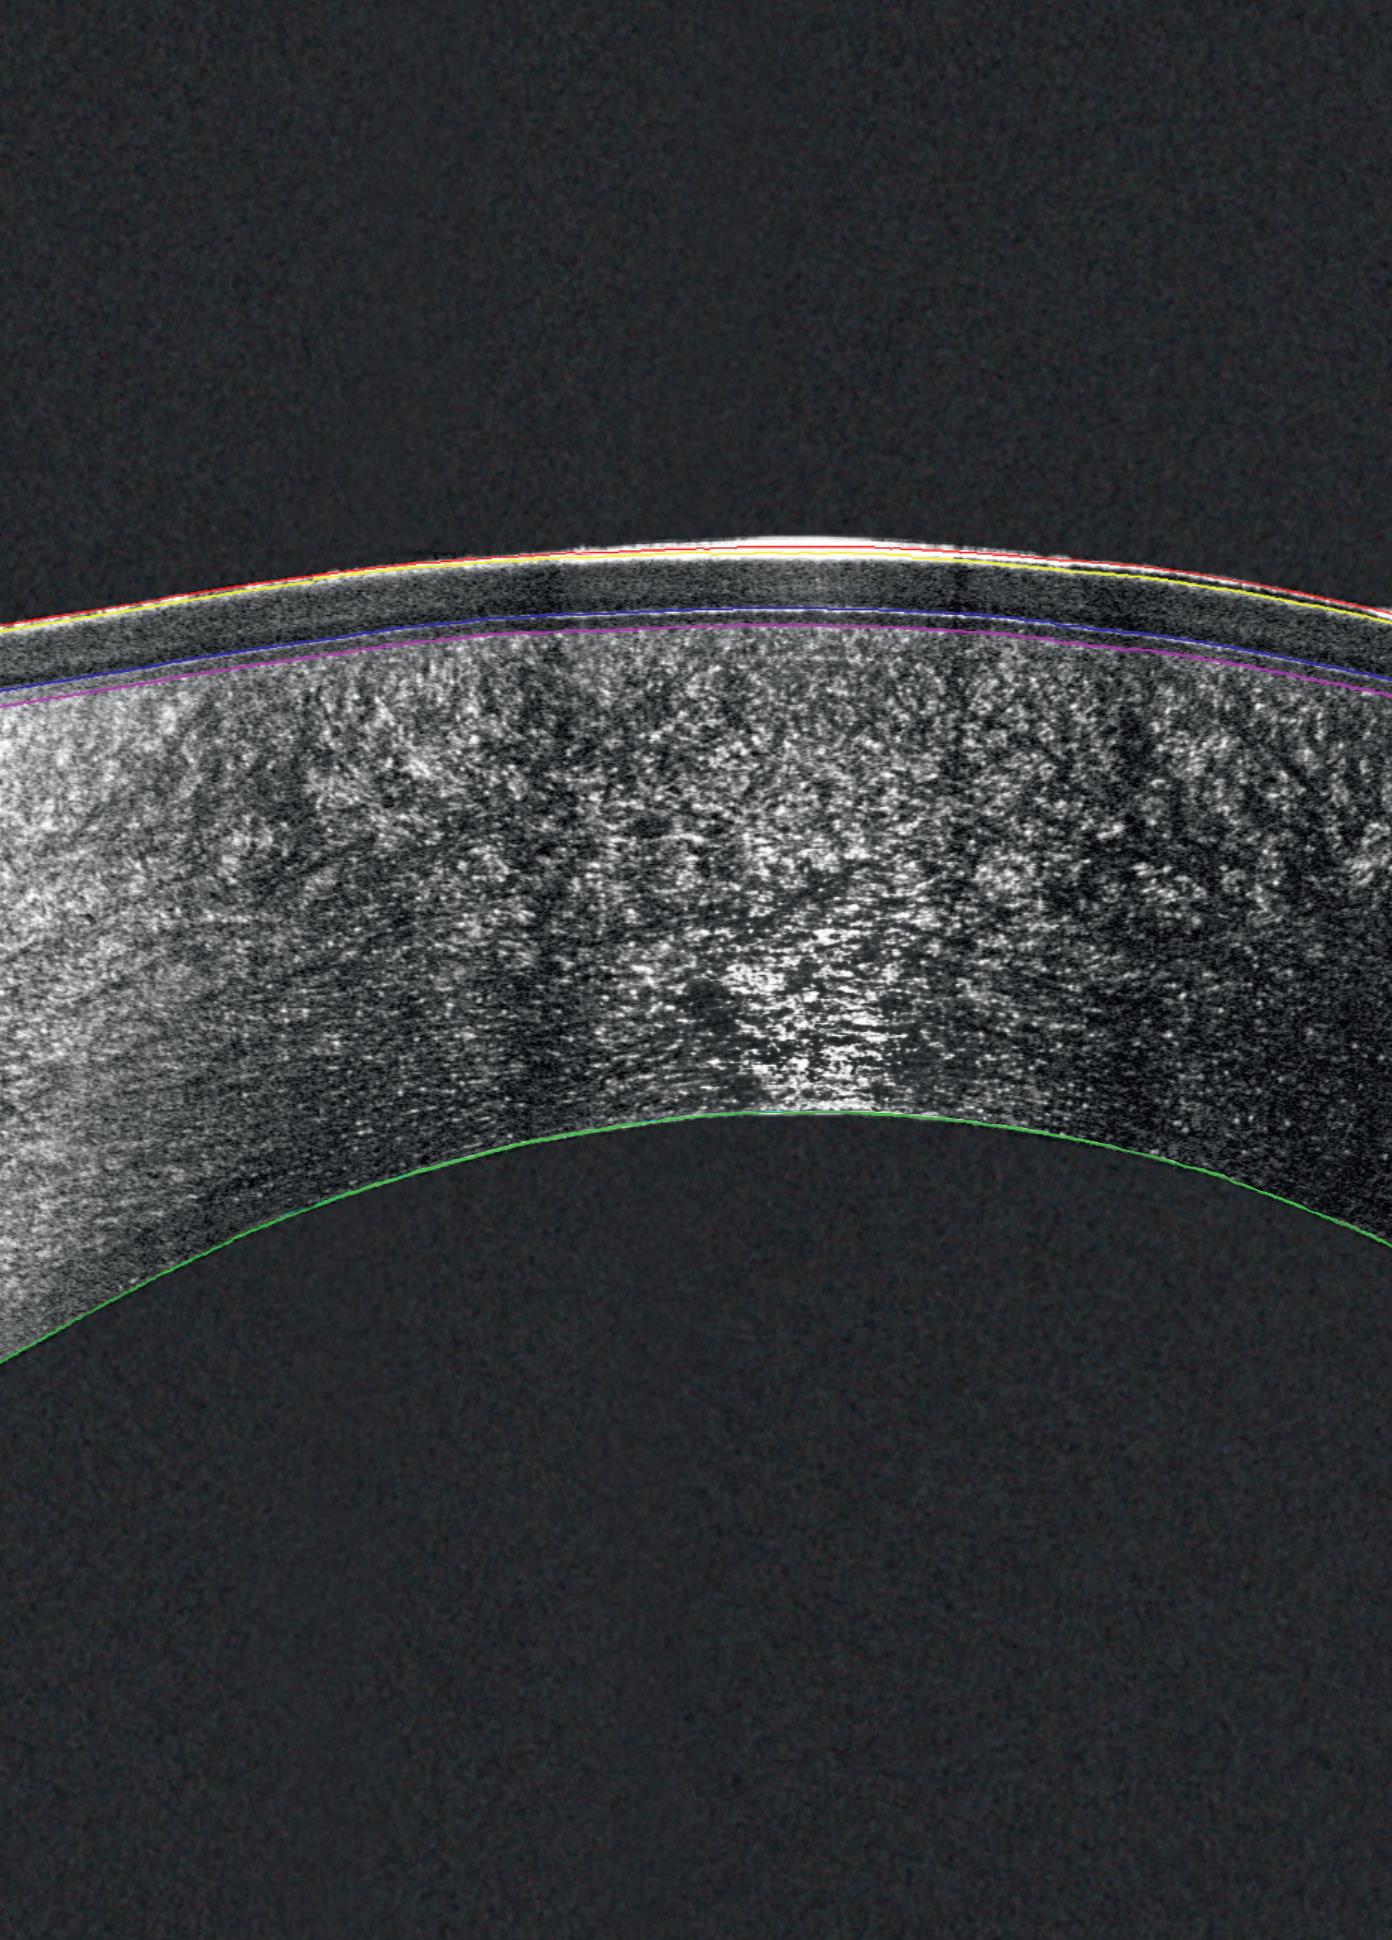

Combining the proven power of Scheimpflug imaging with the precision of ultra high-resolution OCT enables the detection of previously unseen corneal pathologies with unprecedented clarity.

EPITHELIUM

BOWMAN’S LAYER

STROMAL LAYER

The Pentacam® Cornea OCT can increase the confidence that your diagnosis is correct.